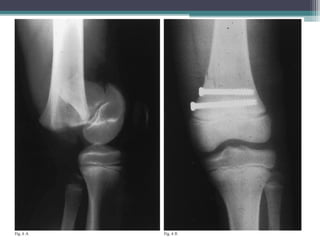

• FOR TYPES 3 & 4

 REQUIRE ANATOMICAL REALIGNMENT VIA ORIF

 ORIF CAN BE WITH LAG SCREWS OR KIRSCHNER

WIRES RUNNING PARALLEL TO PHYSIS